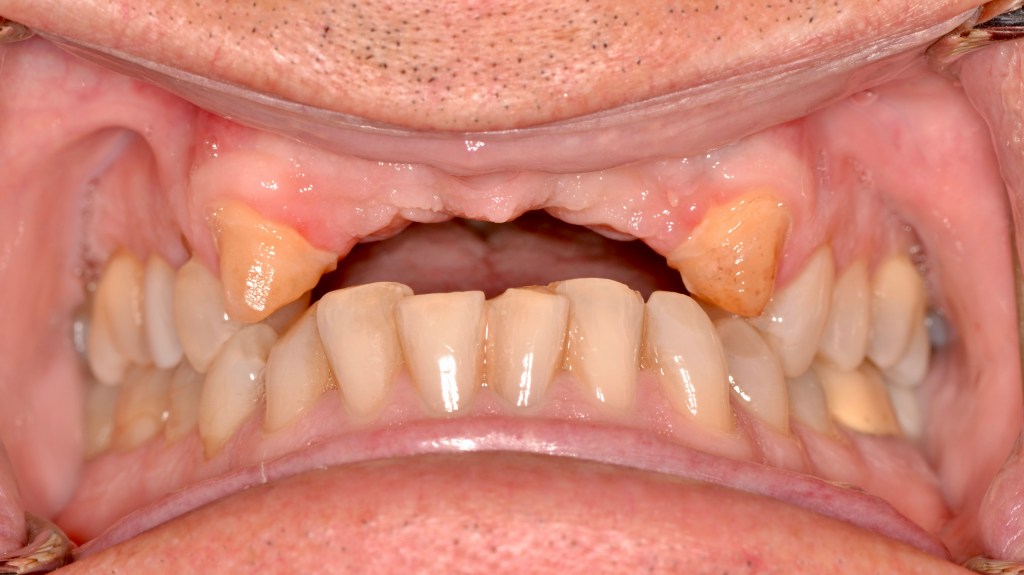

Ceramic Bridge